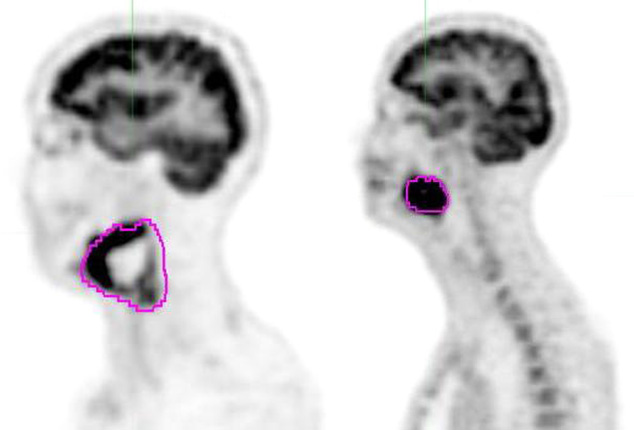

18F-FDG-PET/CT metabolic parameters for diagnostic assessment of tumor biology Streszczenie Wczesne postawienie prawidłowej diagnozy, zwłaszcza w onkologii, pozwala na dobranie najbardziej odpowiedniego leczenia dla pacjenta. Badania radioizotopowe odgrywają kluczową rolę w ocenie czynności narządów i tkanek oraz procesów metabolicznych zachodzących w organizmie człowieka, natomiast mniejszą w ocenie budowy morfologicznej. Pozytonowa tomografia emisyjna (PET) jest nieinwazyjną metodą, która…